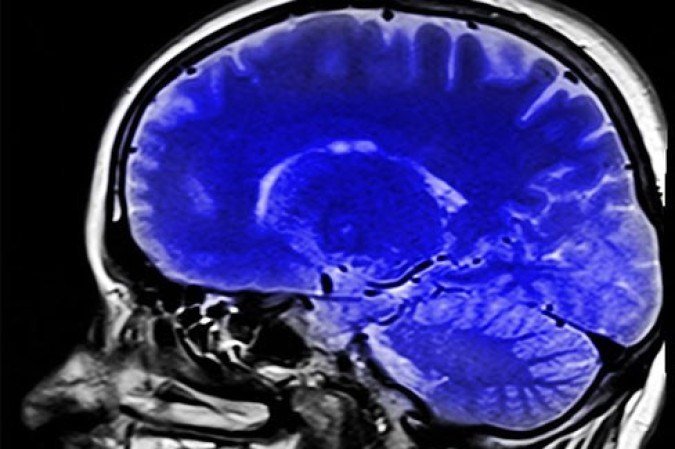

Pesquisadores da Bélgica identificaram uma nova população de células que atuam na proteção do cérebro humano. A descoberta, publicada na revista Nature Neuroscience, amplia a compreensão sobre como o órgão se defende contra substâncias nocivas e processos inflamatórios.

Considerado uma das estruturas mais complexas do corpo humano, o cérebro possui múltiplas barreiras de proteção que funcionam como filtros contra substâncias nocivas e patógenos. Uma das barreiras mais importantes, porém, menos conhecida é o plexo coroide, que envolve e protege o sistema nervoso central.

Para investigar essa questão, pesquisadores do Instituto Vlaams de Biotecnologia (VIB) e da Universidade de Ghent identificaram células chamadas de “células da barreira basal” que funcionam como um “portão inteligente”, formando uma vedação molecular capaz de bloquear até mesmo moléculas pequenas. Elas regulam o que pode atravessar entre o plexo coroide, o líquido cefalorraquidiano e o cérebro.

No entanto, em situações de inflamação sistêmica, essa barreira pode se tornar mais vulnerável, permitindo a entrada de substâncias nocivas no sistema nervoso.

Até então desconhecida, a chamada barreira basal abre uma nova via para entender como o sistema imunológico interage com o cérebro. A descoberta pode contribuir, no futuro, para o desenvolvimento de estratégias capazes de fortalecer essa proteção e auxiliar no tratamento de doenças neurológicas.